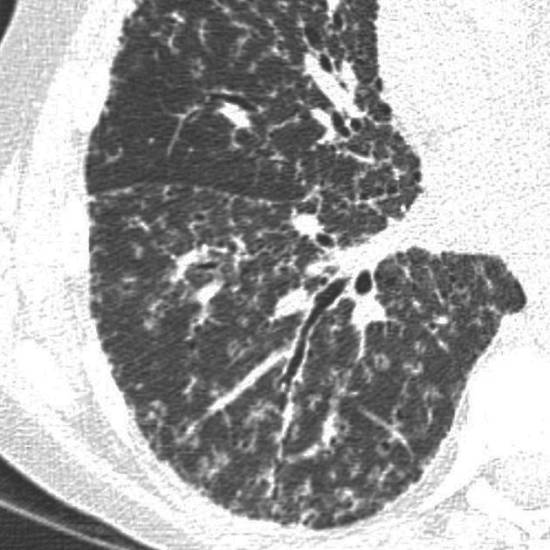

Рентгеносемиотика диссеминированного туберкулеза легких зависит от клинической формы заболевания. Признаками острого процесса служат наличие в обоих легочных полях множественных однотипных очагов, расположенных симметрично, в виде цепочки по ходу сосудов. При подострой диссеминации очаги имеют тенденцию к слиянию, возможно образование полостей распада. Для хронической диссеминации характерно асимметричное расположение очаговых теней, которые имеют разную форму, величину, очертания, интенсивность в зависимости от срока давности их возникновения. Рентгенография легких, как правило, дополняется линейной или компьютерной томографией.

КТ легких при саркоидозе. Множественные очаги, расположенные вдоль центрального интерстиция и плевральных листков, с характерной картиной «четок».